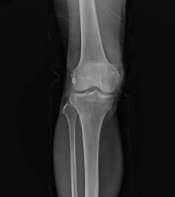

5. 뼈 건강 강화

글루코사민은 뼈의 건강을 유지하는 데 중요한 역할을 합니다. 뼈 조직의 회복을 지원하고 골밀도를 강화하여, 골다공증과 같은 뼈 관련 질환의 위험을 줄이는 데 도움을 줄 수 있습니다.